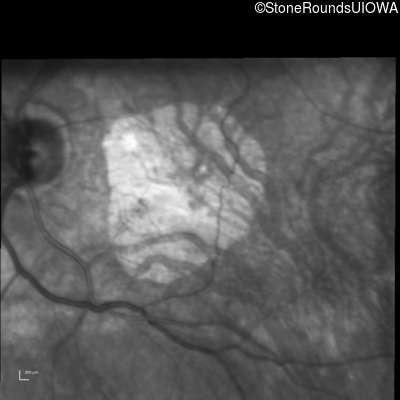

Infrared Fundus Photograph - Right - 20/80

Exemplar

Infrared Fundus Photograph - Left - 20/63